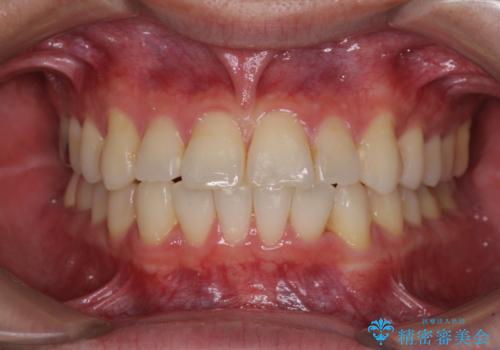

- 以前の矯正治療の後戻りにより、上下の前歯がでこぼこになってしまったことを気にして来院された患者様です。

口元がこれ以上突出することなく前歯の叢生が改善できるよう、歯と歯の間を削ってスペースを獲得し、インビザラインを用いて整えていくこととしました。

目安の装着時間である1日22時間をしっかりと実践してくださり、半年強という短期間で治療を終えることができました。